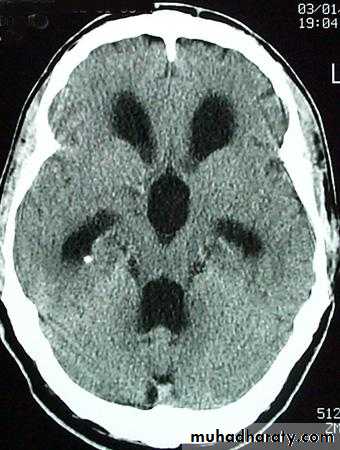

Hydrocephalous

2 types

Obstructive ( non – communicating )

Non –obstructive ( communicating )

No obstruction of the ventricular pathway , but the absorption of the csf at the level of arachnoids' granulation is occluded secondary to lodge by blood clot or inflammatory cell or infection post meningitis most commonly to occur post SAH .